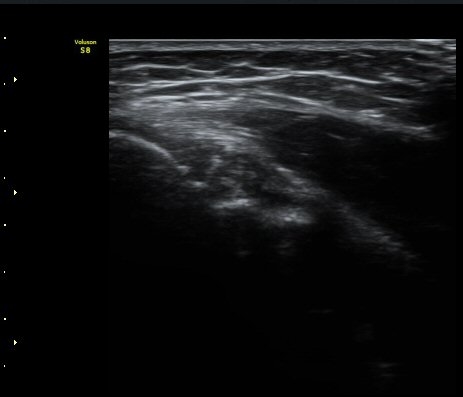

ÃÊÀ½ÆÄ °Ë»ç

³»»ó°ú Á¾´Ü¸é°Ë»ç»ó  ³»ÃøºÎÀδë Àú¿¡ÄÚ ºÎÁ¾°ú ³»»ó°ú ÀÎ´ë ºÎÂøºÎ ÇÇÁú°ñÀÇ ºÒ±ÔÄ¢º¯È­¿Í

°ñÆíÀÌ °üÂûµÇ°í(±×¸² 1, 2, 3, 4) ÀÌ·±¼Ò°ßÀº °ÇÃø°ú ºñ±³ÇÏ¸é ´õ¿í ¶Ñ·ÈÇÔ(±×¸² 5, 6).